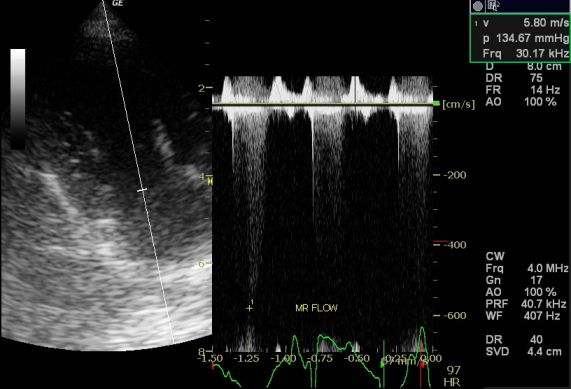

ワクチン時の身体検査にて心雑音が聴取されたワンちゃんの心臓検査を行いました。胸部のX-ray検査にて心拡大があり、心臓の超音波検査を行うと・・・

心臓が収縮しているときに左心房への血液の逆流があり、左心房も健康な個体と比べると大きく拡大しておりましたが、実はそれだけではなくて・・・

なんと、右心房と右心室の間の弁(3尖弁)にも血液の逆流が・・・

なので、この症例の診断名としては僧房弁閉鎖不全(MR)と三尖弁閉鎖不全(TR)ということになります。

幸いにして、今のところ発咳や運動不耐、腹水貯留などの症状は出てはいなかったため、いわゆる心不全という状況までは発展していませんでした。

飼い主さんはできるだけ悪化しないようにしてあげたいということで内科治療を選択していただきました。

これから、毎日の治療が始まりますが、飼い主さんもワンちゃんも頑張っていただきたいものです。